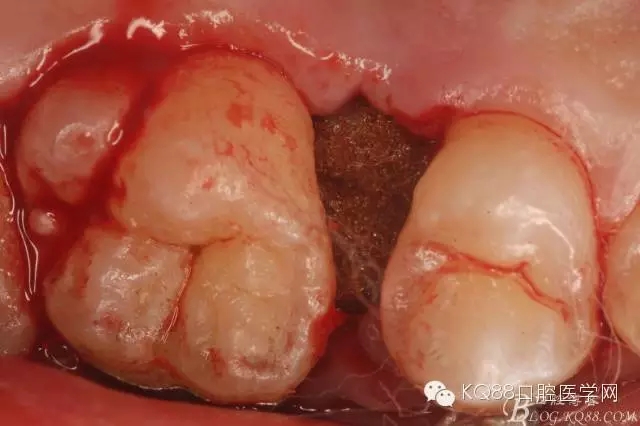

圖21.相鄰牙齒毫發(fā)無損,牙槽窩形態(tài)正常,無破壞。

圖22.牙槽窩內(nèi)放置膠質(zhì)銀止血海綿